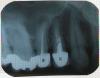

pistons777 Опубликовано 27 января, 2011 Поделиться Опубликовано 27 января, 2011 Здравствйте! Около года был сломан 14 зуб. Корни остались.Собираюсь установить имплант. Доктор планирует одномоментную имплантацию.Хотелось бы спросить у уважаемых докторов на форуме их мнения. Спасибо! Ссылка на комментарий

Bier Опубликовано 28 января, 2011 Поделиться Опубликовано 28 января, 2011 на 5ке - большая гранулема.Я последнее время не любитель одномоментной хирургии. Удаляю, жду 3 мес, ставлю. Ссылка на комментарий

pistons777 Опубликовано 28 января, 2011 Автор Поделиться Опубликовано 28 января, 2011 на 5ке - большая гранулема.Я последнее время не любитель одномоментной хирургии. Удаляю, жду 3 мес, ставлю.5 ка больше 10 лет не беспокоит. Получается нужно лечить 5ку до имплантации 4ки? Спасибо! Ссылка на комментарий

tchena Опубликовано 30 января, 2011 Поделиться Опубликовано 30 января, 2011 получается так.велика вероятность , что гранулема воспалится, если рядом с ней сверлить кость Ссылка на комментарий